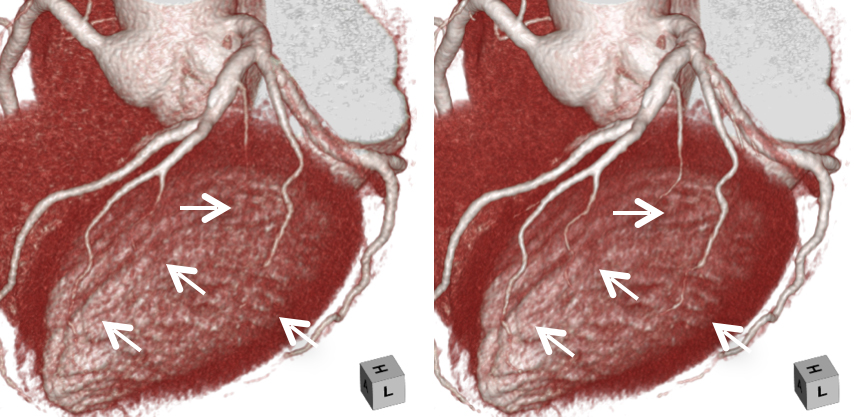

キヤノンメディカルシステムズが開発したPrecise IQ Engine(PIQE)によるディープラーニングの画像によって、冠動脈CT検査で評価が難しい石灰化やステントに接する部分の描出が向上されるため、さらに正確な画像診断が可能となりました。

石灰化症例:左の従来画像と比較して、右の高精細ディープラーニング画像では血管周囲の白い石灰化部分がシャープに描出されています。

ステント症例:左の従来画像と比較して,右の高精細ディープラーニング画像では小さなステントの内部も明瞭に描出されています。

左の従来画像と比較して、右の高精細ディープラーニング画像では矢印の細い血管も明瞭に描出されています。